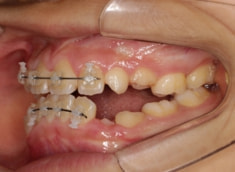

治療法:拡大装置+フルパッシブブラケット(クリアスナップ)+フェイスマスク+舌トレーニング+前歯部エラスティック

治療開始時